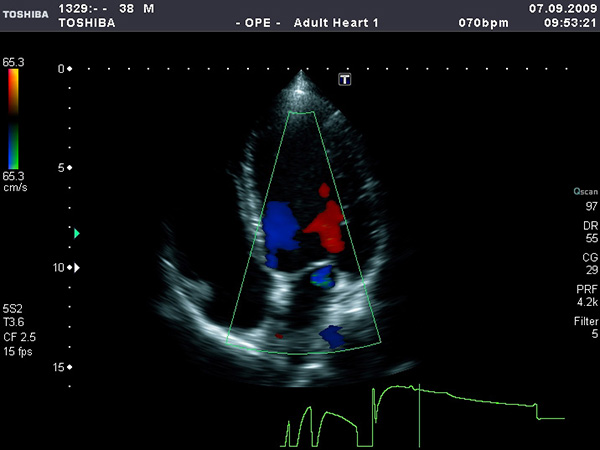

Такой метод диагностики выполняется в двух разных режимах — дуплексном и триплексном. Дуплексное исследование показывает сам сосуд, при этом просматривается проходимость, возможные факторы, которые могут влиять на нарушения в проходимости.

Во время исследования кровотоки «подкрашиваются» красным или синим цветом

С помощью триплексного режима определяется не только внутреннее состояние сосуда, движение кровяных телец окрашивается в яркие цвета, все это видно на экране. С помощью триплексного сканирования возможно получить наиболее точную информацию.